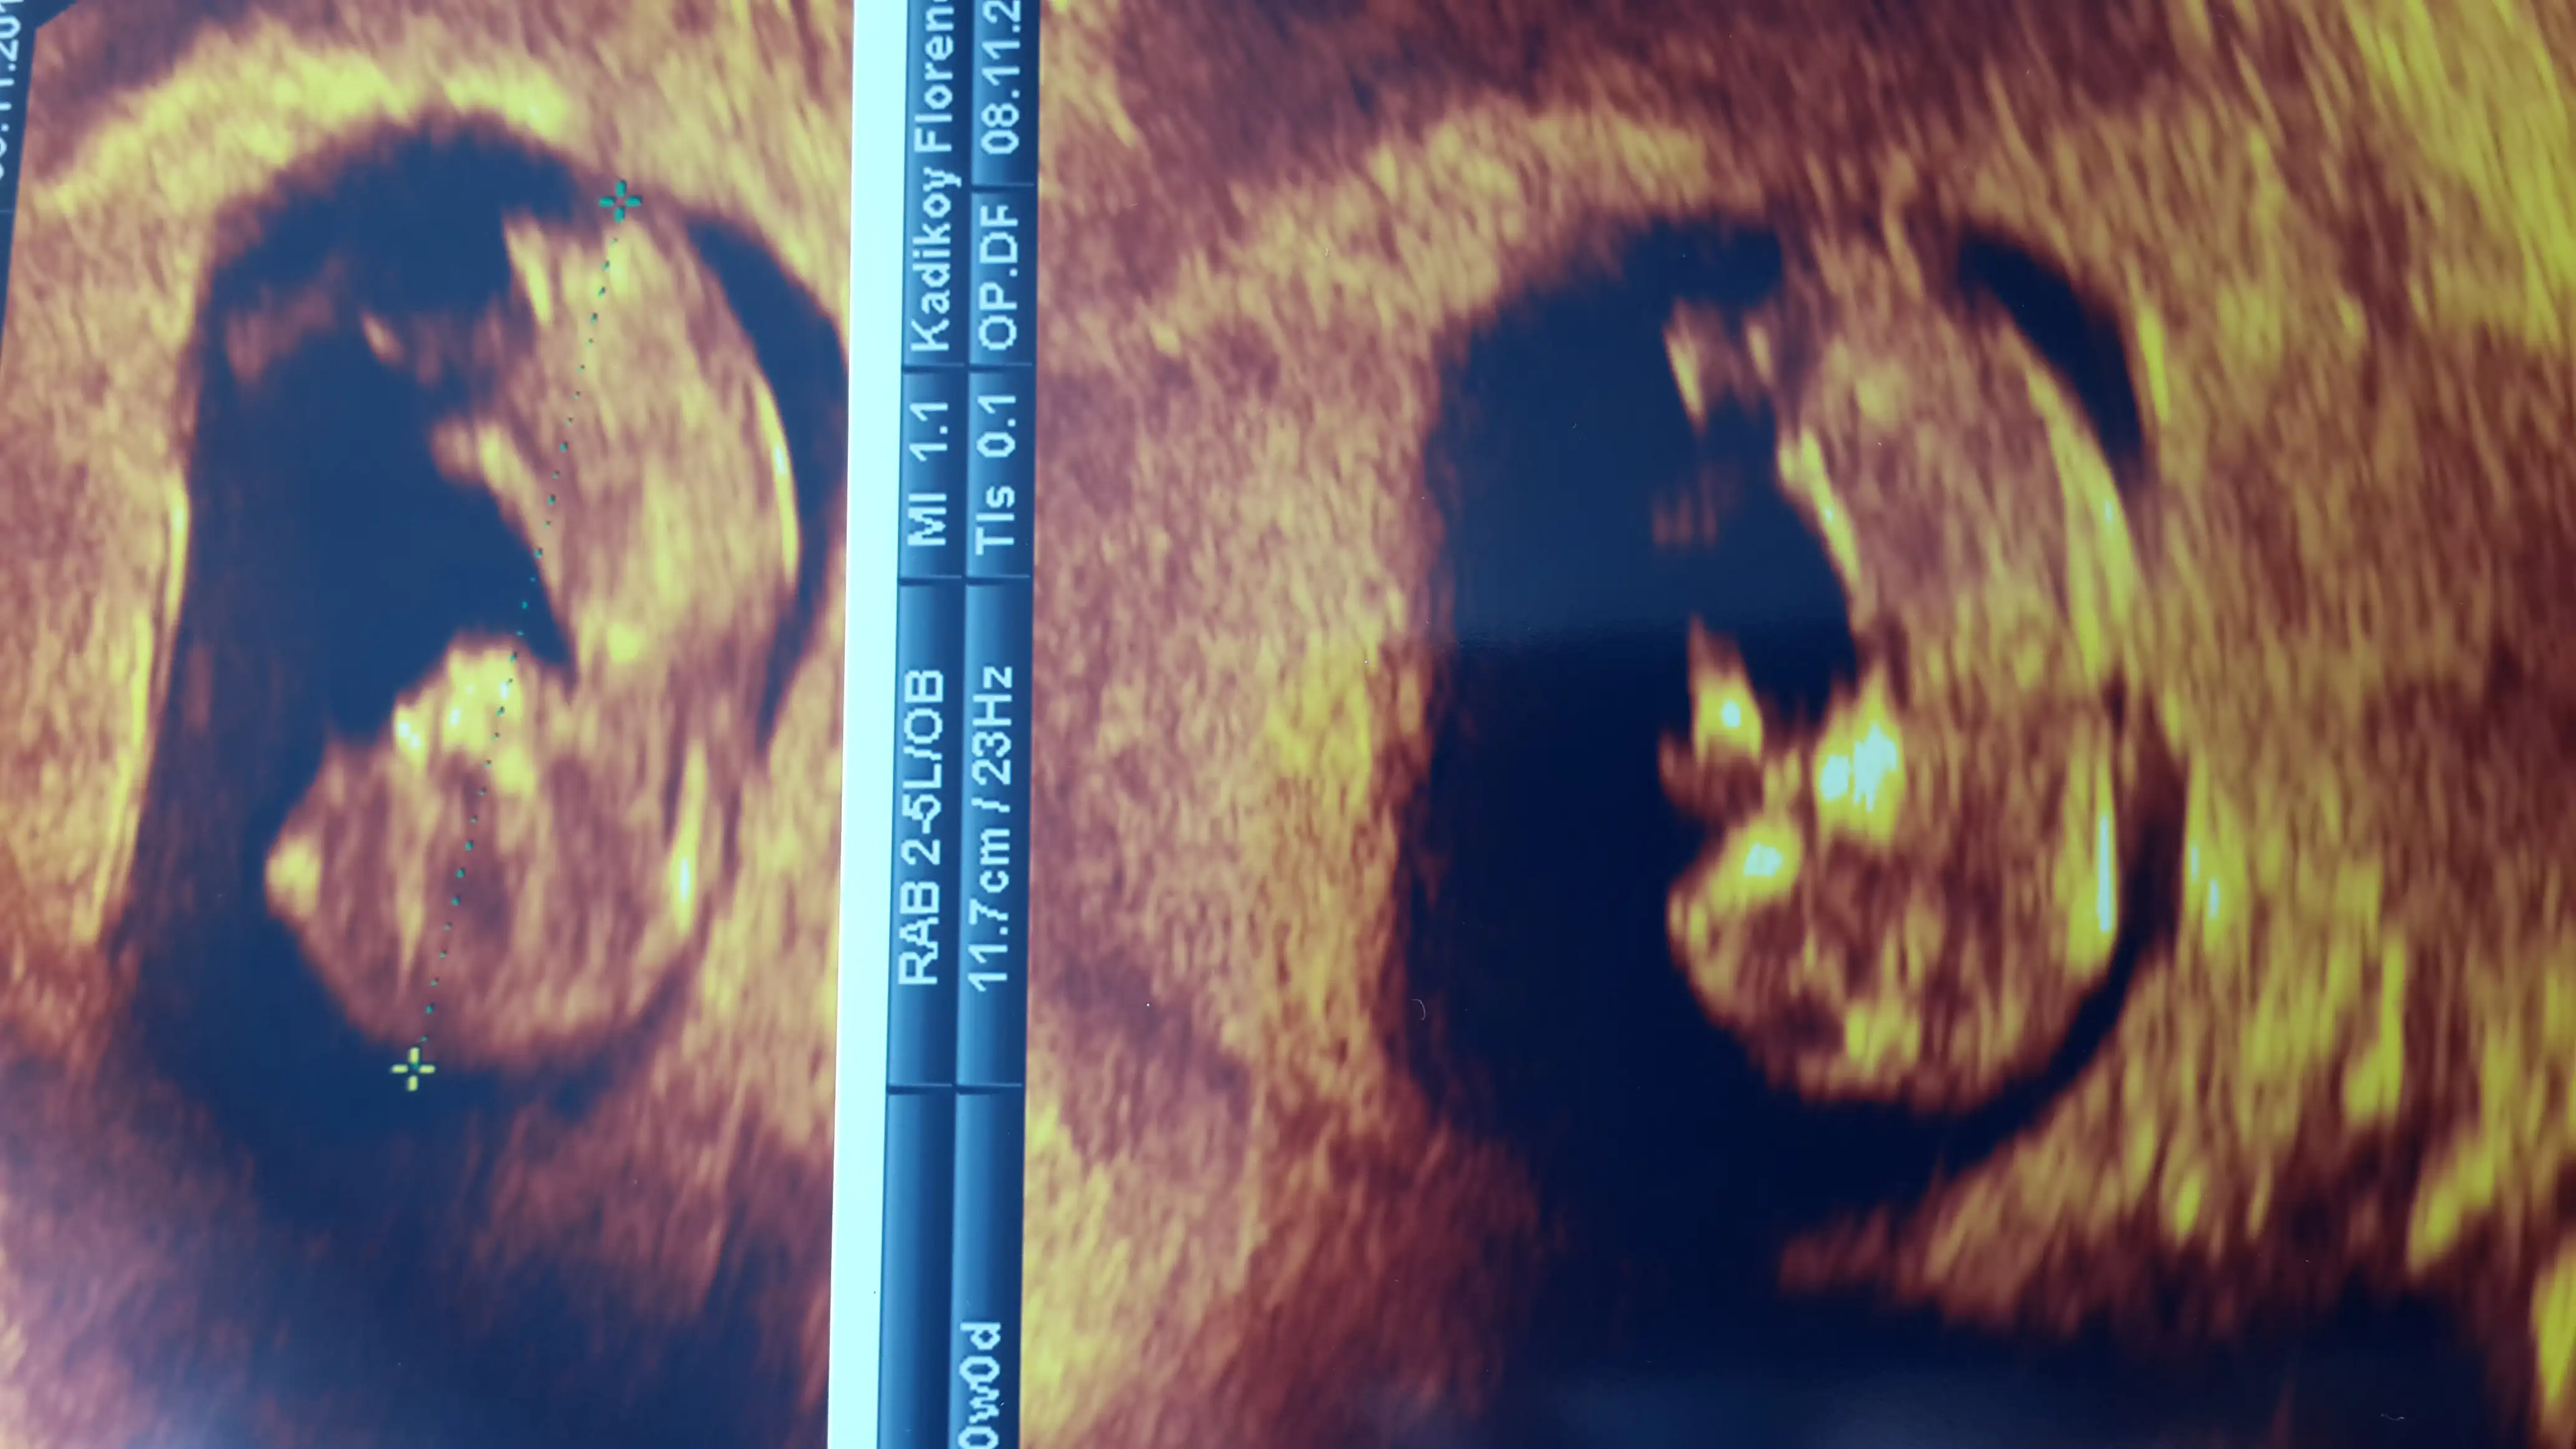

bu haftada nub nerdeyse aynı oluyor cnm en iyi tahmin 12 13 te illa bi yorum yap dersen kız gibi geldi bence iki hafta sabret yeni foto koyCanim benimkinede bakabilirmisin 10+3uz burda Eki Görüntüle 1297431 Eki Görüntüle 1297432